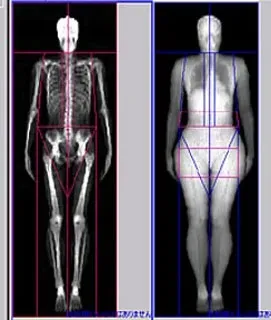

◆当院では新しい骨密度測定装置を設置し、骨がスカスカになる

骨粗しょう症の診断及び治療を行なっております。

◆しかも当院の装置は、人体を3物質に大別して(骨、脂肪、非脂肪)測定可能な装置です。

メタボリックシンドローム・ロコモティブシンドローム・スポーツ医学の分野でも有用です。

◆検査は、約5~10分以内で行なえ、痛みもありません。

腰の骨や大腿骨の骨の骨密度を丁寧に測定し、今後の治療や対策を考えます。